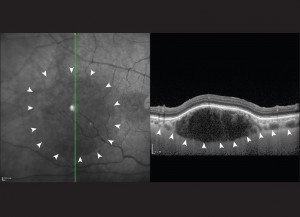

Fig. 7. Angioma della coroide